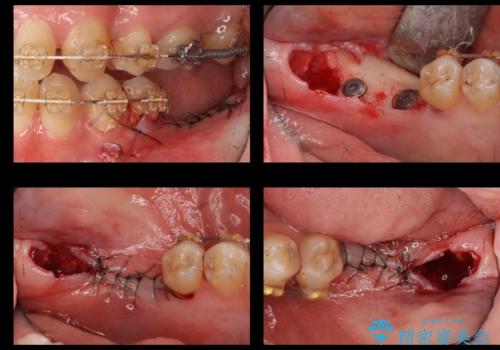

- 奥歯が二本欠損しており、その奥に親知らずが残っていました。

インプラントの一時手術と親知らずの抜歯を同時にしています。

親知らずはだいぶ後方にあり使うことが難しいため抜歯しています。